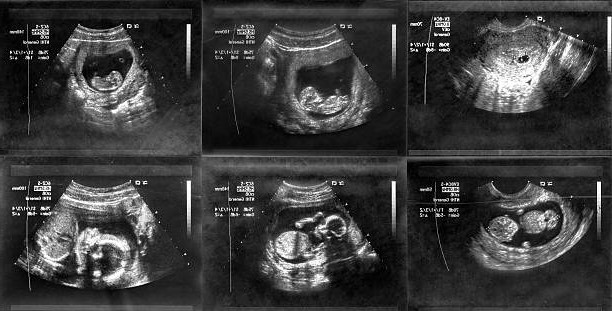

В период начала УЗ-исследований, когда архаичная аппаратура могла реально нанести непоправимый вред плоду, ученых справок о точном характере вреда этого обследования не было. Для научной базы требовались годы наблюдений за детьми, рожденными после утробного УЗИ-обследования. Шли годы, но аппаратура успела измениться до неузнаваемости. Исчезла ли опасность данного обследования для беременных? Оказывается, не совсем.

Ученые из Вашингтонского Университета занялись данной проблемой вплотную. Перед специалистами стояла задача с практически двумя неизвестными: является ли аутизм врожденным вследствие УЗ-обследования плода, и может ли в принципе УЗИ направленно приводить к аутизму у детей? Результаты обследования оказались неоднозначными, но общего категоричного вывода ученые сделать не смогли. Зато они установили точную взаимосвязь между двумя явлениями в жизни беременной на стадии вынашивания, и в первые годы жизни ребенка.

В целом, картина предсказуема. Если на генетическом уровне у ребенка вероятно возникновение аутических расстройств, то с большой долей вероятности их дополнит или пробудит УЗИ в первый триместр беременности.

В ходе обследования детей из более чем 2000 семей, американские ученые пришли к выводу, что картина с аутизмом, имеющим вероятным происхождением УЗИ в первый триместр беременности, в разных случаях — разная. Одни дети с аутизмом подавлены и практически не адаптированы в социальную среду, другие наоборот, весьма активны и коммуникабельны в пределах нормы для своего возраста.

Как показали статистические данные обследований, в 7 процентах случаев тяжелой формы аутизма имело место ультразвуковое обследование плода в первый триместр беременности. Медицинские учреждения и организации США, работающие в сфере перинатальных центров и системе здравоохранения, связанные с женским здоровьем и беременностью, настоятельно рекомендуют избегать ультразвукового обследования в первый триместр беременности, если это не серьезная ситуация.